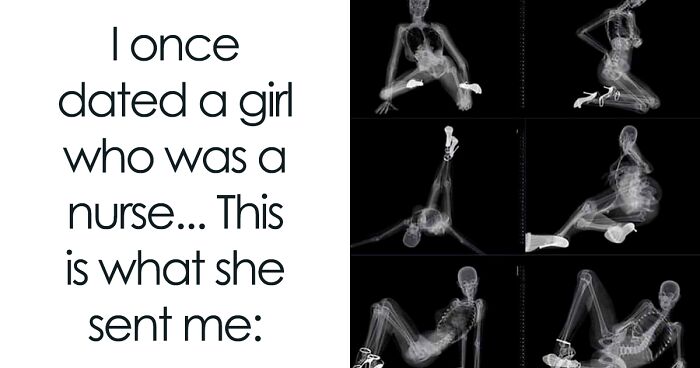

The human body is capable of astonishing things, and many medical stories remind us how unpredictable biology can be. You might have heard of cases where an ordinary hospital room became the setting for quiet endurance, revealing how much a person can withstand.

One hub for such stories is the subreddit r/medizzy, where people share captivating cases and the scenes behind medical care. The community looks at conditions that puzzle even seasoned experts while highlighting the daily dedication of doctors. These posts mix science with compassion, showing the fragile yet resilient side of life. Keep reading to explore medical cases that reveal the complexity of health and healing.